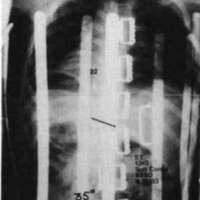

Figure 7. The diagrams on the left illustrate the similarity between the spinal column in the case of an uncontrolled pelvis and the slender column pin-jointed (free to tilt) at its lower end. The two diagrams on the right illustrate the similarity between the controlled pelvic case and the built-in base end condition.To fully appreciate the strength of this scheme in practice, compare the two x-rays in Fig. 8a and Fig. 8b. Fig. 8a is the x-ray taken just before the pelvic leveling procedure was performed and Fig. 8b is the x-ray taken a few minutes later, after the pelvic leveling procedure was performed. The Cobb angle is reduced from 36 degrees to 20 degrees by this quick procedure, which is normally performed as a routine part of positioning the child in the sitting support orthosis. These x-rays are of a boy with Duchenne Muscular Dystrophy; he was not wearing a corset.

Figure 8a. An x-ray taken just before the pelvic leveling procedure was performed.Figure 8b. The x-ray taken a few minutes later after the procedure.

A second example is given in Fig. 9. The left and center x-rays show the progression which occurred in the eight months following fitting. During this period, the parents did not use the pelvic leveling procedure. The x-ray on the right was taken a short time after the center x-ray, with the only difference being the pelvic leveling procedure was performed before the last film. Note: once a spine deformity has become partially structural, the pelvis can be leveled only to the degree that the deformity is still flexible.

Figure 9. The left and center x-rays show the progression which occured in eight months following a fitting. During this period, the parents did not use the pelvic leveling procedure. The x-ray on the right was taken a short time after the center x-ray, and after the pelvic leveling procedure was performed.In summary, maintaining a level pelvis makes it easier to control the spine. Pelvic control and orientation in the frontal plane also relates strongly to the uniformity of pressures in weight bearing areas and minimizing the progressive deterioration of sitting comfort.